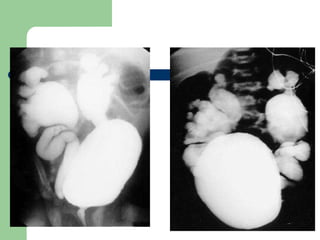

ESTUDIOS POR IMAGEN Solo si se sospecha de infección renal o alteración anatómica. Rx de riñón, uréteres y vejiga, cistouretrografía miccional, ecografía renal, UVI, TAC y Gammagrafía. Exploraciones especiales: cistoscopia y en ocasiones pielografía retrograda para descartar uropatía obstructiva.

ESTUDIOS POR IMAGENSolo si se sospecha de infección renal o alteración anatómica. Rx de riñón, uréteres y vejiga, cistouretrografía miccional, ecografía renal, UVI, TAC y Gammagrafía. Exploraciones especiales: cistoscopia y en ocasiones pielografía retrograda para descartar uropatía obstructiva.